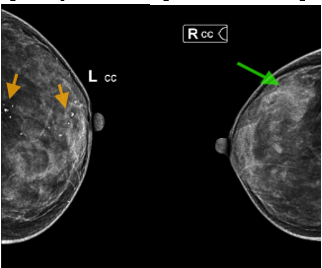

- Chụp cắt lớp vi tính ngực: Nốt bán đặc thùy dưới phổi phải ~6mm, các ổ ngấm thuốc kém hai vú, kích thước ~14x11mm

Hình 3. Hình ảnh CT lồng ngực: Ổ ngấm thuốc kém vú trái (vòng tròn vàng)